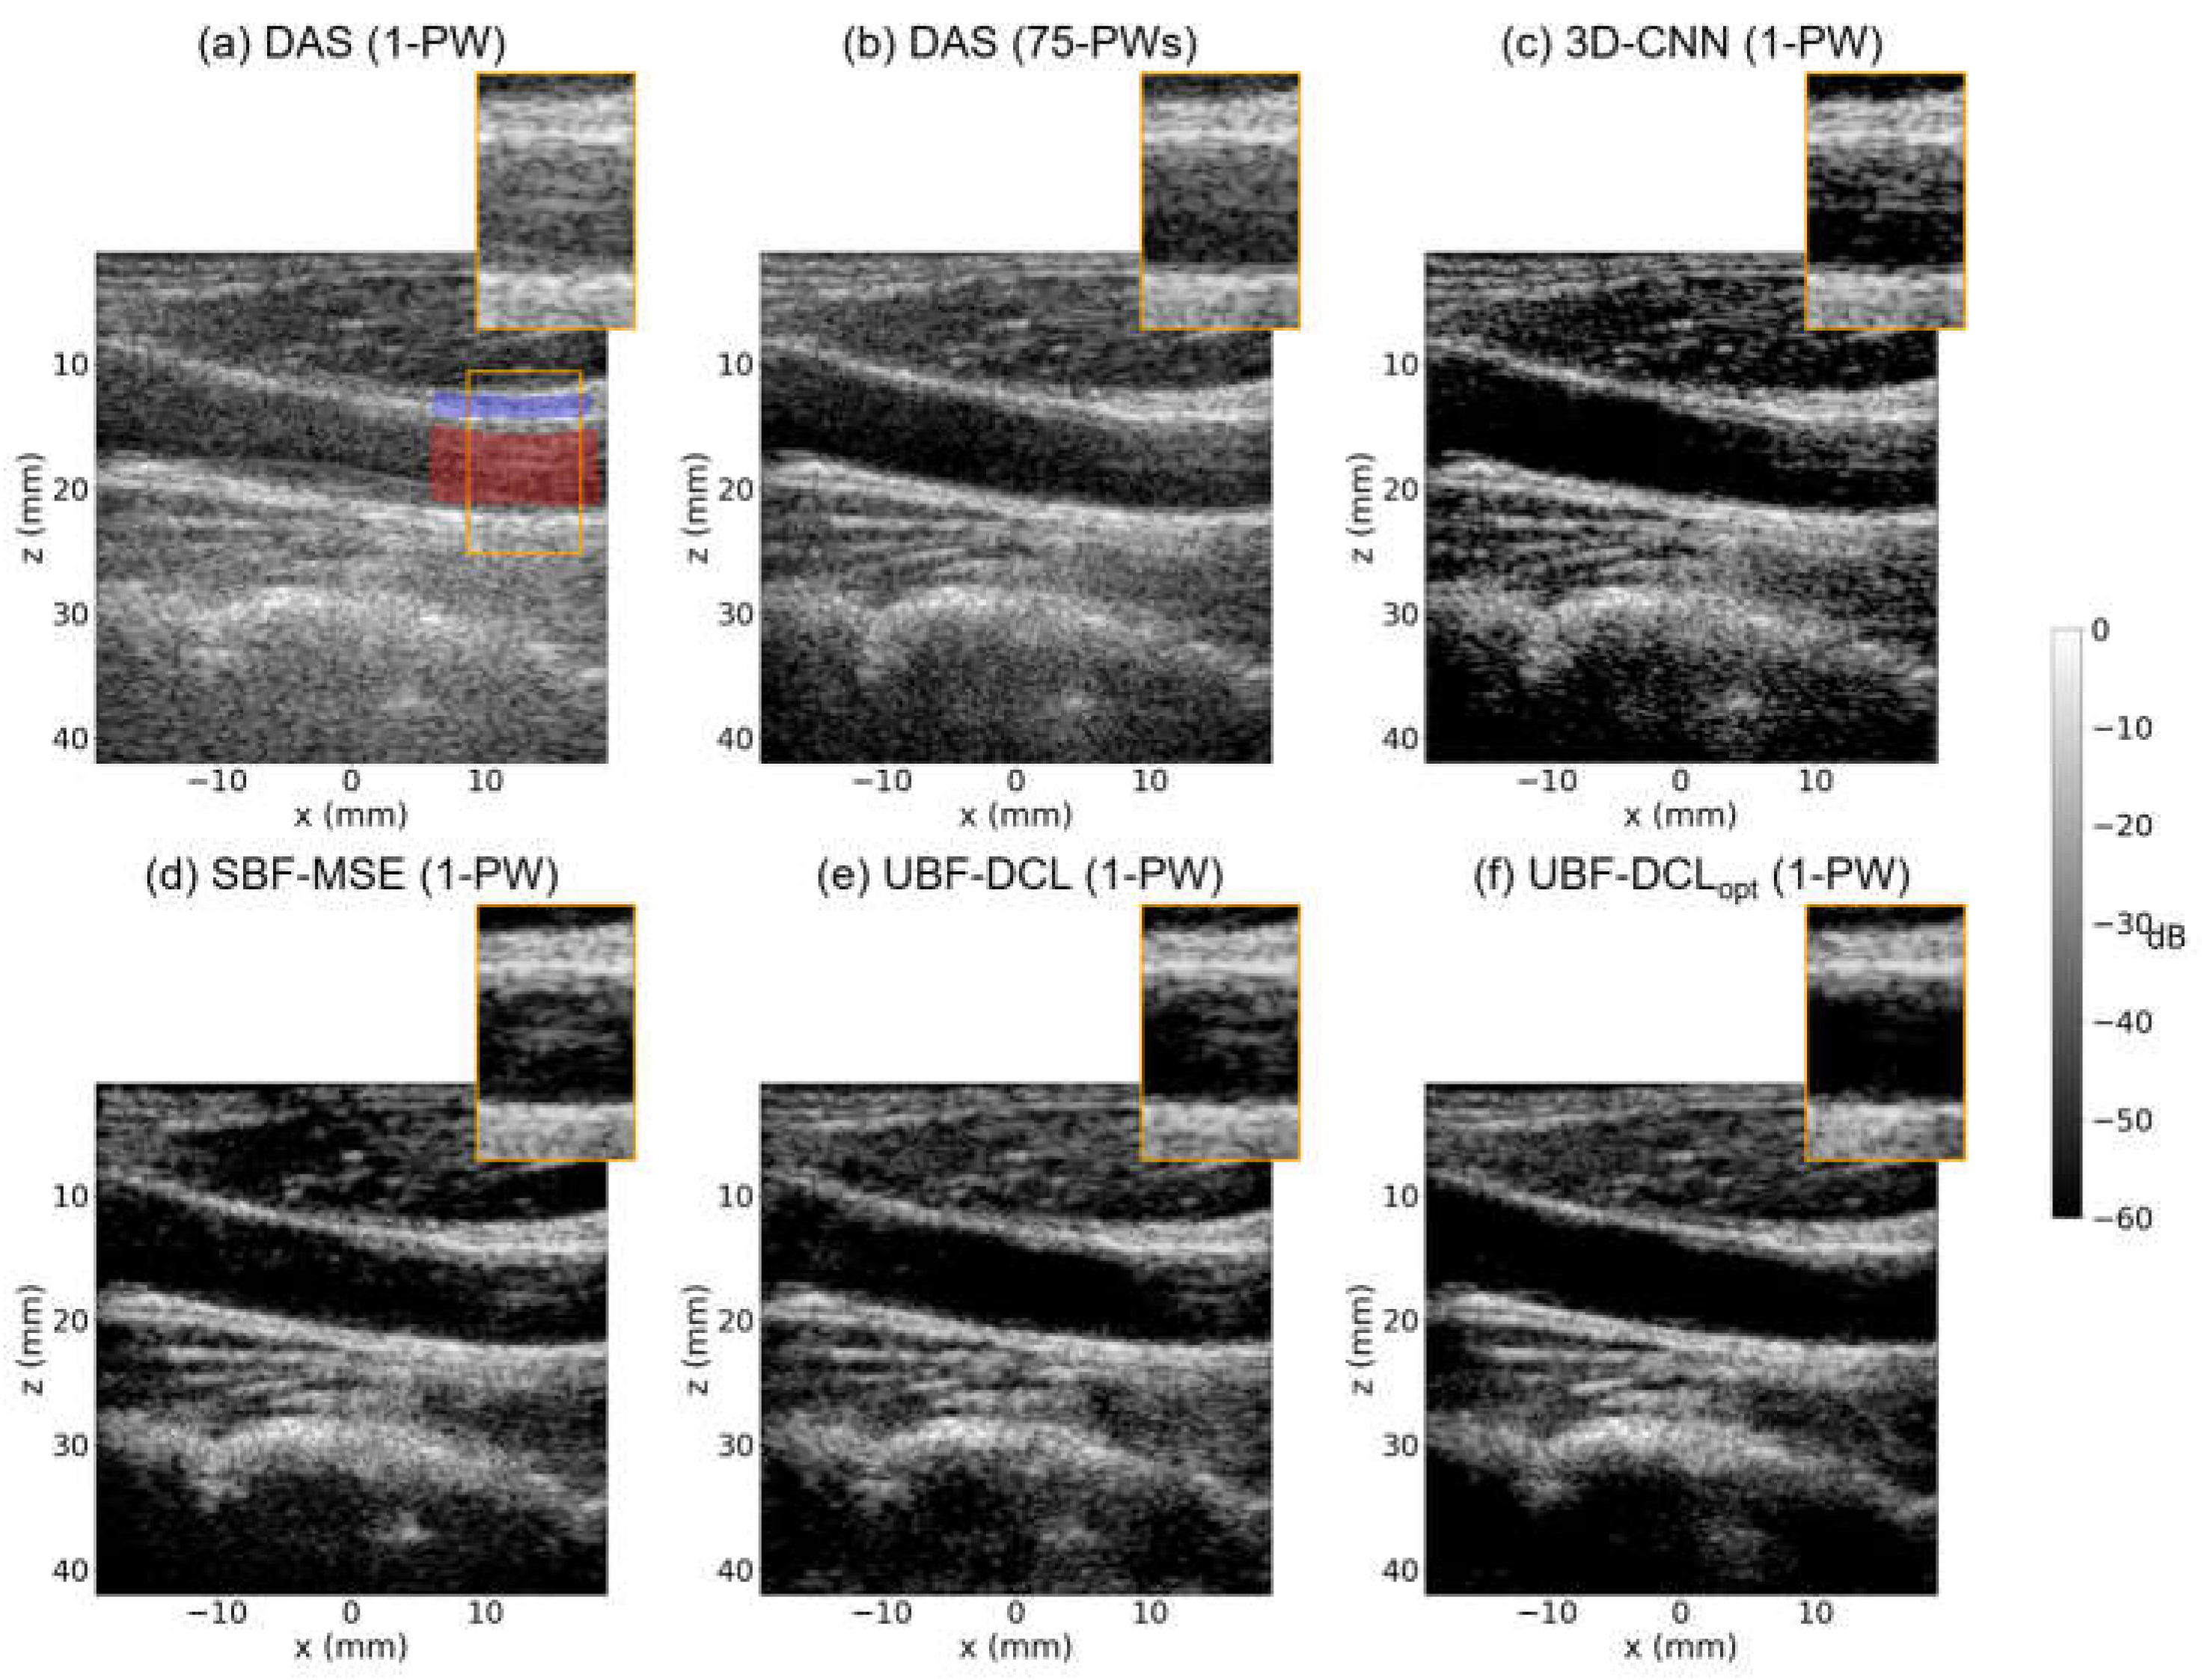

Figure 6 presents B-mode images reconstructed using DAS (1 PW), DAS (75 PWs), 3-D CNN (1 PW), UBF-DCL (1 PW), and UBF-DCLopt (1 PW) in the cross-sectional view of another ex vivo clutter artifact phantom (D = 20 mm). Figure 6a shows the SPWI image reconstructed using DAS beamforming, which suffers from severe clutter artifacts caused by multipath reverberation echoes, resulting in poorly defined boundaries and low image quality. On the other hand, DAS with 75 PWs demonstrates improved PWI image quality through coherent compounding of multiple plane-wave transmissions. However, reverberation artifacts with high spatial correlation across the compounded plane waves remain clearly visible, as depicted in Figure 6b. The DL-based clutter suppression approach using the 3-D CNN shows limited improvement over DAS with 1 PW, retaining noticeable reverberation artifacts, as shown in Figure 6c. Figure 6d shows the SBF-MSE results obtained using MSE loss with a 75-angle DAS reconstruction as the ground truth. This supervised approach achieved moderate clutter artifact suppression; however, the imperfect nature of the 75-angle DAS reference data limits its effectiveness, as evidenced by residual artifacts within the anechoic target region. The UBF-DCL method achieves substantial clutter suppression with reduced reverberation compared to the DAS (75 PWs), 3-D CNN, and SBF-MSE methods; however, residual artifacts remain visible within the anechoic target region, as illustrated in Figure 6e. Figure 6f shows the proposed UBF-DCLopt result and it demonstrates substantially enhanced clutter suppression, yielding clearly defined target boundaries while preserving the structural integrity of the background tissue regions.

Figure 6. Reconstructed B-mode images using (a) DAS (1-PW), (b) DAS (75-PWs), (c) 3-D CNN (1-PW), (d) SBF-MSE (1-PW), (e) UBF-DCL (1-PW), and (f) UBF-DCLopt (1-PW) in the cross-sectional view of the ex vivo clutter artifact phantom (D = 20 mm). The red and blue areas in the ROI were employed for CNR and gCNR measurement.

The third row in Table 2 lists the measured CNR and gCNR values for the six comparison methods, calculated using the red and blue regions indicated in Figure 6a. As shown in Table 2, DAS with 75 PWs exhibits higher CNR and gCNR values than DAS with 1 PW and the 3-D CNN methods, and shows performance comparable to that of the SBF-MSE method. However, both DAS with 75 PWs and SBF-MSE method underperforms the UBF-DCL method, in which the fixed coherence loss effectively identifies subtle decorrelated clutter artifact signals between PW frames. On the other hand, the proposed UBF-DCLopt achieved a CNR of 2.82 dB and a gCNR of 0.87, corresponding to a 25% improvement in CNR and a 7.4% improvement in gCNR over the UBF-DCL method.

The last row in Table 2 shows the measured CNR and gCNR values averaged over the entire 25-frame clutter phantom datasets, which consist of two different imaging orientations (longitudinal and cross-sectional views) for each of three different diameters (D = 10, 15, and 20 mm). As listed in Table 2, DAS with 75 PWs outperformed DAS with 1 PW and 3-D CNN methods; however, it showed lower performance than the SBF-MSE and the two unsupervised methods (UBF-DCL and UBF-DCLopt). Among the six comparisons, UBF-DCLopt exhibited the highest CNR and gCNR values, i.e., averaging 3.47 and 0.91, respectively, indicating an 11.9% increase in CNR and a 7.1% increase in gCNR compared with UBF-DCL.